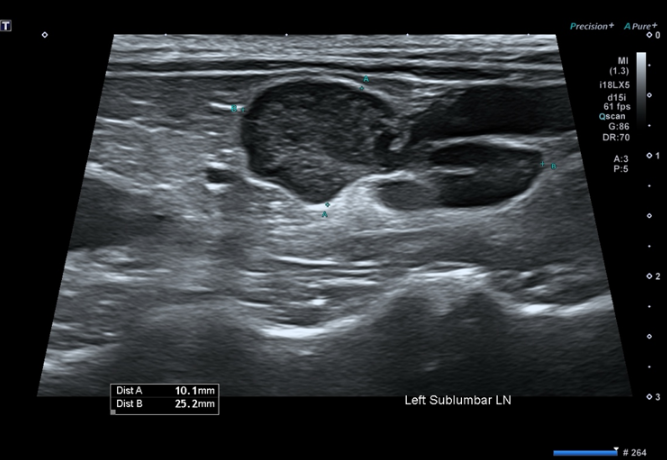

그림 1. 복부 초음파에서 확인된 요추하 림프절 비대

체표 및 복강 내 다발성 림프절 비대 확인

비장에서 벌집 징후(honeycomb sign) 관찰

→ 종양에서 특징적으로 보일 수 있는 소견